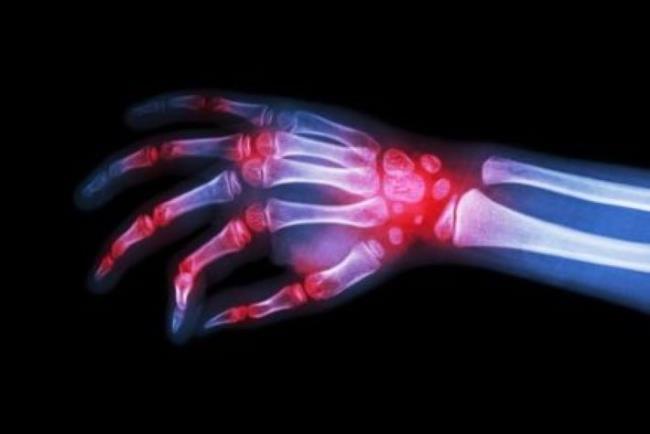

אורנסיה היא תרופה ביולוגית אנטי דלקתית המשמשת כקו טיפול שני לחולי דלקת פרקים ראומטית, או דלקת מפרקים ספחתית פעילה. התרופה הוכחה כמפחיתה בצורה משמעותית את תסמיני המחלה השונים, כמו כאבי מפרקים ונפיחות ומשפרת את טווח התנועה ואת התפקוד היום יומי. מעכבת את התקדמות הנזק המבני ומשפרת את התפקוד הגופני. בנוסף מניעת התקדמות המחלה, מפחיתה את הסיכון לנזקים כרוניים וארוכי טווח.

צילום רנטגן